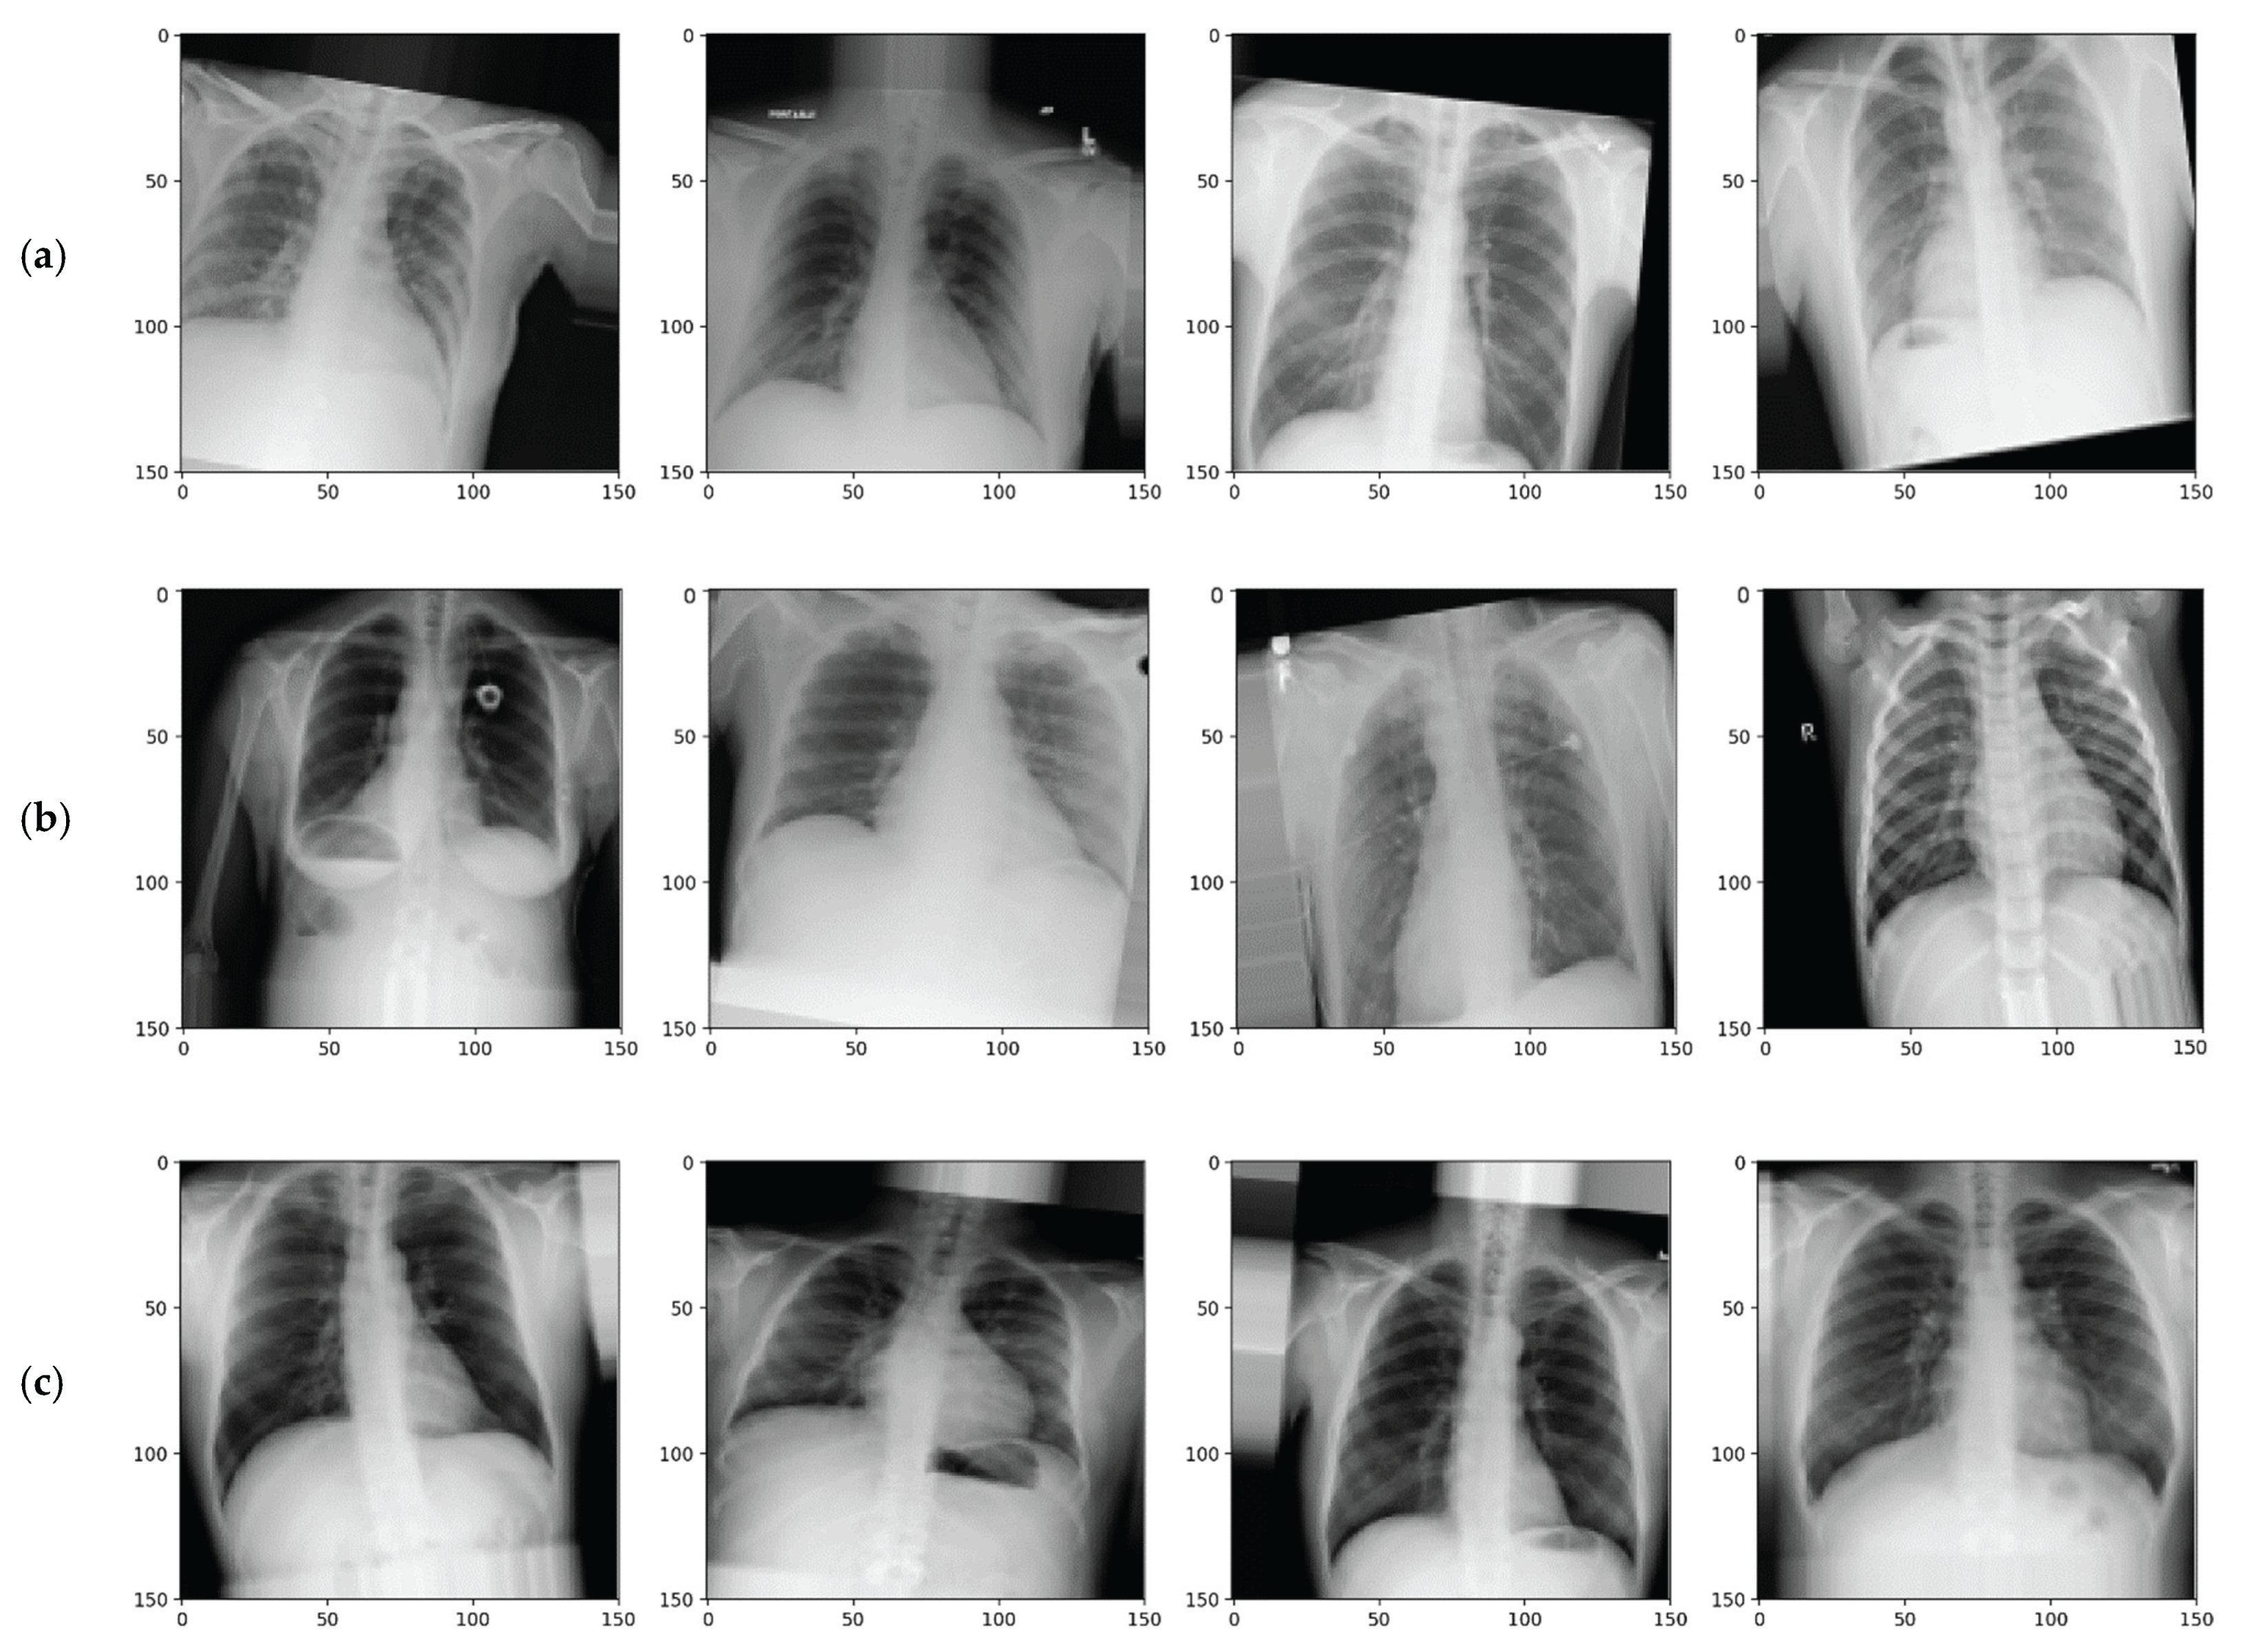

3. Experiments and Results

3.1. Experimental Setup